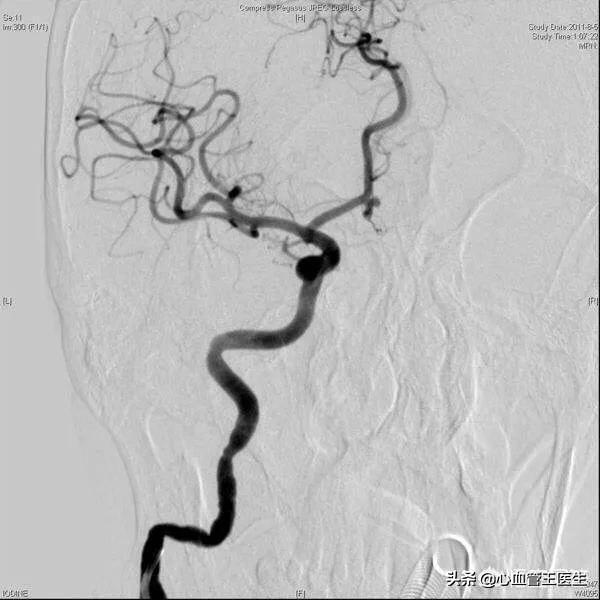

(脳梗塞)(診断のポイント)1、原病変があり、それに対応する成績。2、発症は急性で、頭痛、嘔吐、一過性の意識障害、大動脈塞栓症であれば、昏睡に陥ることもあり、重症例では、閉じこめられたけいれん発作が見られることもある。3、大脳中大脳動脈系の繋留部(症状、徴候、徴候は脳血栓症と同じ)。4、空気塞栓症では、頭痛、吐き気、めまいが急速に現れ、その後、盲目、呼吸困難、チアノーゼ、けいれんなどの症状が現れる。脂肪塞栓症は、多くは骨折後数時間で発症し、しばしば肺繋留として現れ、咳嗽、呼吸困難、チアノーゼ、頻脈が現れ、次いでせん妄、痙攣、昏睡、皮膚点状出血、尿中脂肪粒子などが現れる。(脳血栓症) (診断のポイント) 1、1~2日前に日常的な前駆症状:頭痛、めまい、手足のしびれ、記憶障害、言語障害など 2、多くは睡眠中に起こり、目覚めると口が曲がっている、ろれつが回らない、単麻痺、片麻痺など 3、多くは意識がある 4、バイタルサインに明らかな変化がない 5、脳脊髄液に明らかな変化がない 6、CTで低密度病変を認め、局在がわかる 7、脳脊髄液に変化がない 8、脳脊髄液に変化がない 9、脳脊髄液に著変がない 11、脳血圧に著変がない 12、脳血圧に著変がない。